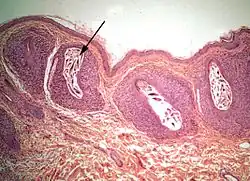

The diagram Mite infestation sites on skin shows where typical infestations of different taxonomic groups mites on livestock animals occur on or in the host's skin.[9] The position of these mites in relation to the skin or other organs is crucial for their feeding and also for their veterinary diagnosis and options for treatment. The mites either feed on the tissues of the skin using penetrating mouthparts or on the inflammatory exudate that results from the action of the mouthparts and saliva of the mites on the skin.[12] Demodectic mites have mouthparts adapted to penetrate and suck out the contents of individual cells of hair follicles.[13] It is usual for all active stages of the mite lifecycle to feed as parasites, but the trombiculid mites are an exception. Most of the parasitic mites do not feed directly on blood, but the dermanyssid mites and larval trombiculid mites directly suck up capillary blood as their exclusive food. The tube through which food is ingested and saliva excreted during feeding is formed in most mites by apposing the sheath that contains the chelicerae against the hypostome. However, the trombiculids are an exception. Some species of mites (Analgidae) have adapted to feeding on keratin and skin debris amongst the feathers of birds, and other species have adapted to feed directly on internal tissues such as air-sacs or lungs (Cytoditidae and Laminosioptidae). Psoroptic mites feed superficially at the stratum corneum; the photograph of a histological section of skin infested with Psoroptes ovis, and the photograph of the surface of a host's skin infested with P. ovis looking like white dots, show this type of feeding. Sarcoptic mites feed by burrowing within the living layers of the epidermis, mainly stratum spinosum. Demodectic mites feed in a position technically external to the skin, between the epidermis and the hair shaft in hair follicles. Dermanyssid and trombiculid mites feed whilst external to the skin by piercing the skin with, respectively, their chelicerae or a stylostome feeding tube. Mites at other sites feed by using their chelicerae to scrape either at the skin surface, or at base of feather, or to penetrate and scrape at internal tissue such as air-sac or lung.

Sarcoptic skin disease

Sarcoptic mites as adults are microscopic, nearly circular in outline, and their legs are short, adapted for burrowing.[30] The females, after mating with males on the surface of their host's skin, burrow into the living layers of the epidermis (mainly the stratum spinosum). They make tunnels horizontal to the surface of the skin. Here, eggs are laid and development of larvae and nymphs occurs. The mites have low mobility and transmission between hosts occurs only during close contact.[31] The feeding of the mites and their excretory products irritates and inflames the skin, causing intense pruritus. Dermal hypersensitivity reactions develop in the host. Chronic infestations lead to thickening of the skin by overproduction of epidermal cells (acanthosis), resulting in a characteristic depilated and scaly appearance. Stress caused by the pruritus can be severe, and will result in 6% to 23% lost productivity of commercially reared pigs.[32][33] Camels are prone to severe infestation with Sarcoptes.[34]